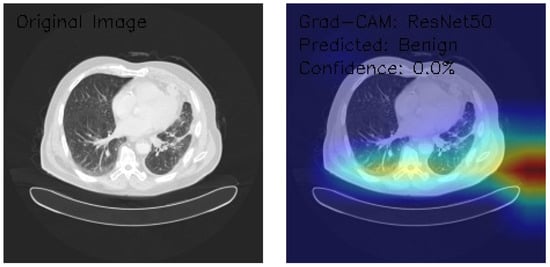

ResNet50 Deep Learning Model

The three axial chest CT images were analyzed using a state-of-the-art ResNet50 deep learning model, a widely recognized convolutional neural network architecture known for its robust performance in image classification tasks. Grad-CAM visualization was employed to gain insights into the model’s decision-making process. This technique provides a detailed heatmap overlay on the original images, highlighting the regions of interest that contributed most significantly to the classification decisions. This combined approach enables accurate classification and offers interpretability, ensuring that the underlying rationale for the model’s predictions can be understood and validated in a clinical context.

Figure 6 demonstrates normal lung parenchyma with a central mediastinal structure. The Grad-CAM heatmap shows predominant activation in the right lateral lung field, indicated by the yellow-red colorization. The model classified this as Benign with minimal confidence (0.0%), suggesting potential limitations in the model’s decision-making process.

Figure 6.

Grad-CAM visualization using ResNet50 for lung CT analysis. (Source: author’s analysis from data, 2024).

Figure 7 shows that the image reveals similar anatomical structures with slightly different density patterns. The Grad-CAM activation is most prominent in the central and right posterior regions, displaying intense activation patterns (yellow-red areas). Despite the visible features, the model again classified this as Benign with 0.0% confidence, indicating potential model uncertainty.

Figure 7.

Grad-CAM visualization using ResNet50 for lung CT scan showing benign prediction. (Source: author’s analysis from data, 2024).

Figure 8 shows an image of distinct parenchymal patterns, particularly in the central and peripheral regions. The Grad-CAM heatmap demonstrates strong activation in the central mediastinal region, extending into the right lung field. Notably, this was classified as Malignant with 0.0% confidence, representing a shift in classification despite the low confidence score.

Figure 8.

Grad-CAM visualization using ResNet50 for lung CT scan with benign prediction. (Source: author’s analysis from data, 2024).

This analysis evaluates the application of ResNet50 with Grad-CAM visualization on three axial chest CT images, focusing on the model’s regions of interest and classification confidence. Grad-CAM heatmaps highlight consistent activation in central thoracic and lung structures, with bilateral asymmetry and variable peripheral attention. Image classifications include two Benign (Images 1 and 2) and one Malignant (Image 3), all with 0.0% confidence, indicating significant uncertainty in the model’s predictions. These results reveal model calibration and reliability issues despite its ability to identify relevant anatomical features. To enhance clinical applicability, recommendations include recalibrating the confidence scoring system, expanding the training dataset, incorporating ensemble methods, and validating results with expert radiologists. This analysis underscores the need to refine the model further to improve its diagnostic reliability and confidence.